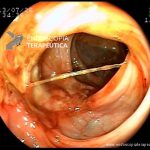

- Doença de Crohn em remissão – pseudopólipo